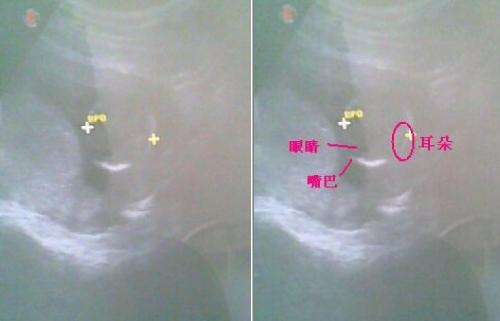

怀孕三个月胎儿图片

怀孕三个月胎儿